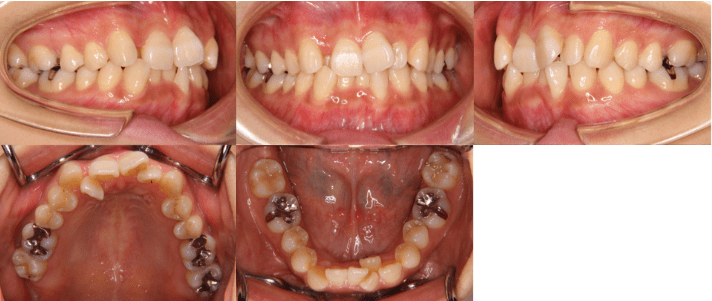

<治療前>

<治療後>

初診時年齢 25歳7ヶ月

主訴 前歯のガタガタ

診断 交叉咬合を伴う叢生症例

治療内容 小臼歯4本を抜歯した後、インビザラインを使用して主訴である叢生の改善を行いました。

治療期間 2年

リスク 矯正治療による歯の移動に伴う痛み、歯根吸収、虫歯

費用 80万円